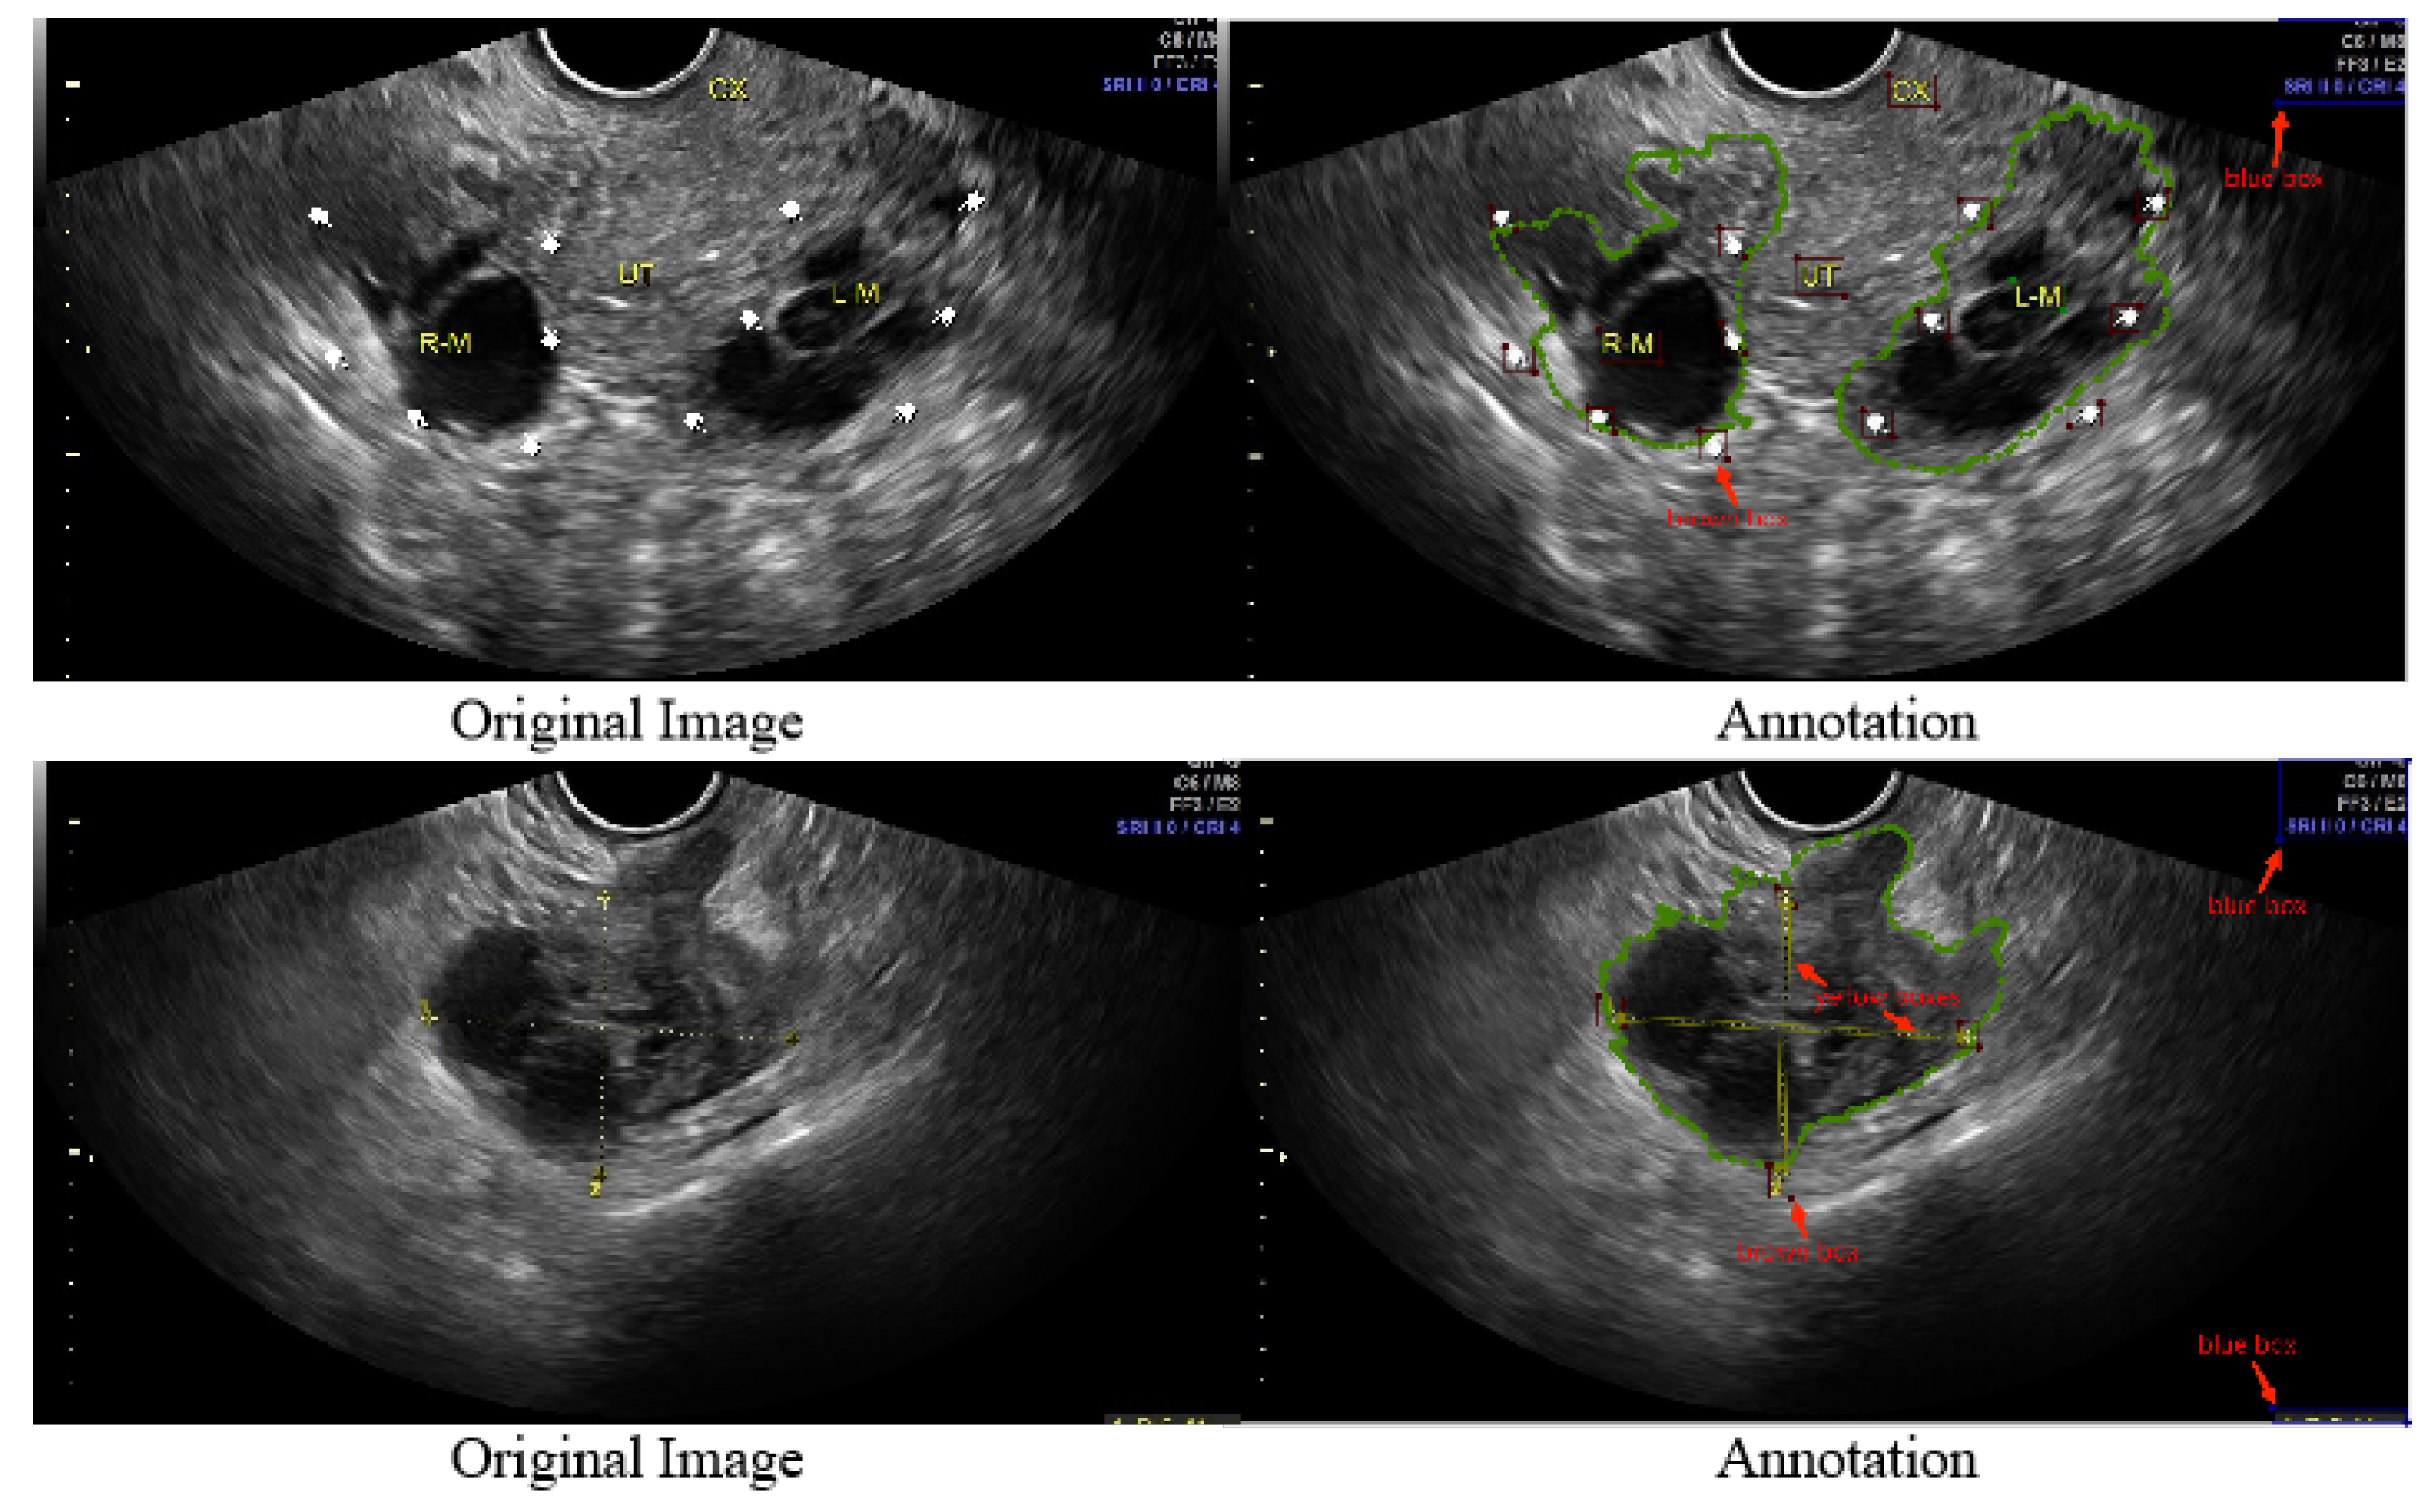

Normal Ovary Ultrasound

Discover how an ovarian cancer ultrasound serves as a vital diagnostic tool for early detection. Learn about transvaginal ultrasound imaging, the role of pelvic exams, and how specialists interpret pelvic masses to assess potential malignancy. Understand the imaging procedures and accuracy of ultrasound technology in identifying ovarian abnormalities to ensure timely medical intervention and improved patient outcomes.

TitleNormal Ovary Ultrasound

Read full article: Ovarian Cancer Ultrasound